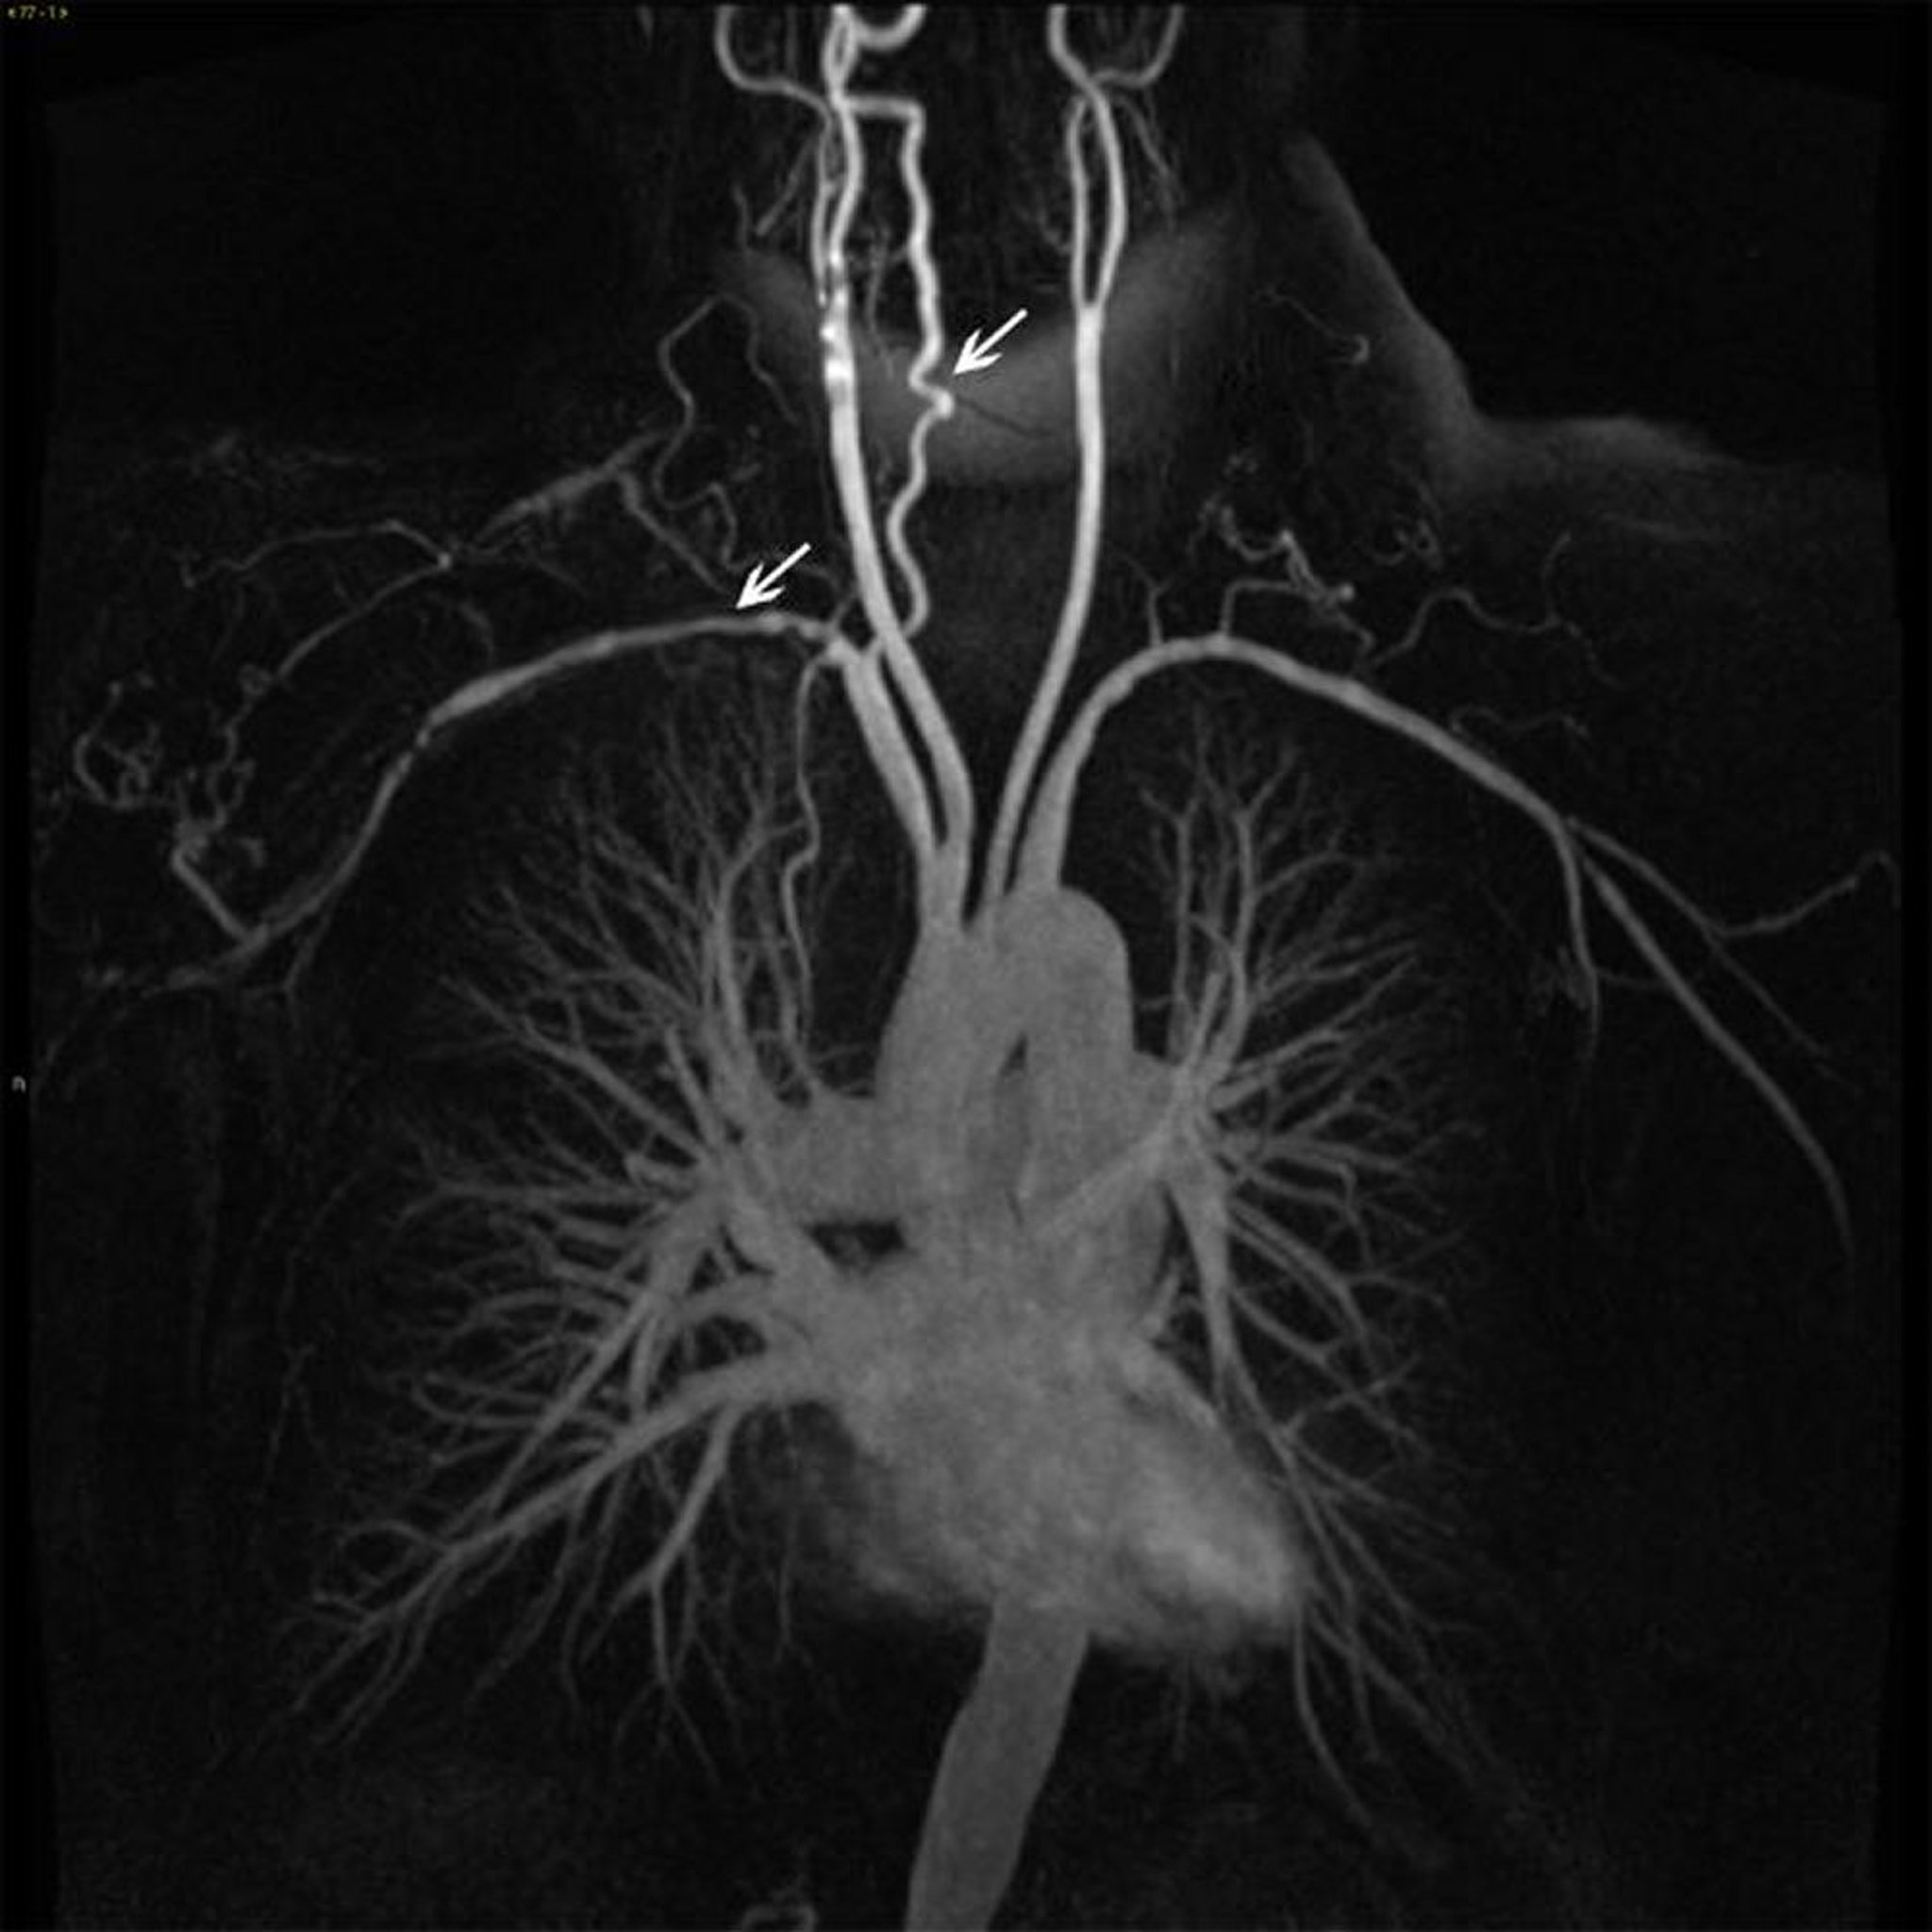

Branches of Ascending Thoracic Aorta in a Patient with Takayasu Arteritis

This image shows mural irregularity and narrowing (white arrows) in several branches of the ascending aorta.